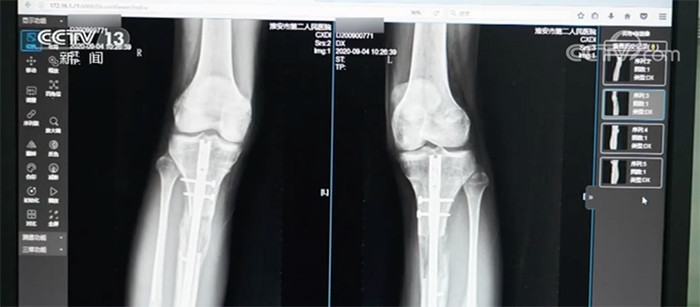

Ngoài Tiểu Hi và Tiểu An, có không ít người khác phải gánh chịu hậu quả nặng nề sau phẫu thuật tăng chiều cao. Năm 2020, Bệnh viện Nhân dân số 2, thành phố Hoài An, Giang Tô (Trung Quốc) tiếp nhận một bệnh nhân nam 22 tuổi. Vì không hài lòng với chiều cao của mình, anh đã ra nước ngoài làm phẫu thuật kéo dài chân và sau đó là đôi chân bị nhiễm trùng nặng. Anh không thể đi lại, thậm chí còn phải đối mặt với nguy cơ tàn tật suốt đời.

Đôi chân của bệnh nhân nam 22 tuổi sau phẫu thuật kéo dài chân. (Ảnh: Jxnews)